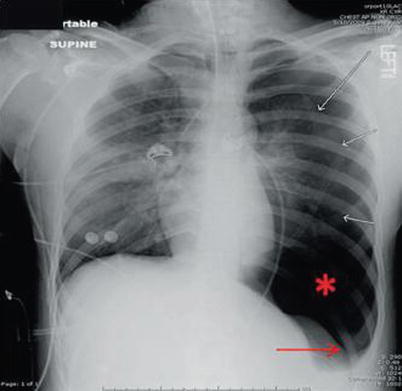

Fig. 15.3

Image of a large left pneumothorax after line placement. Visceral-pleural line clearly seen (white arrows), with a hyperlucent upper abdomen (red asterisk) and deep sulcus sign (red arrow)

Pneumothoraces are common complications after penetrating thoracic injury and occur secondary to disruption of the alveoli and lung parenchyma leading to leakage of gas into the interstitial space. The most frequent radiographic finding is the “visceral-pleural line” (Fig. 15.3) in the apical-lateral lung field representing separation of the normally apposed visceral and parietal pleura. Pneumomediastinum is also frequently encountered and is most commonly due to pulmonary-alveolar rupture. These radiographic signs can vary from subtle findings to gross abnormalities. Trauma patients are often in the supine or semirecumbent position when the portable chest x-ray is acquired. In these positions, it has been reported that up to 30 % of pneumothoraces are not visualized. Patient positioning can be changed to increase radiographic sensitivity but is often not feasible in the trauma setting. Instead you should be aware of other places that the pneumothorax may be visualized, namely, the anteromedial and subpulmonic recesses (Fig. 15.4). Other less common imaging findings present with a pneumothorax include a hyperlucent upper abdomen, sharply demarcated diaphragm, demarcation of the inferior surface of the lung, and the “deep sulcus sign” (Fig. 15.3).